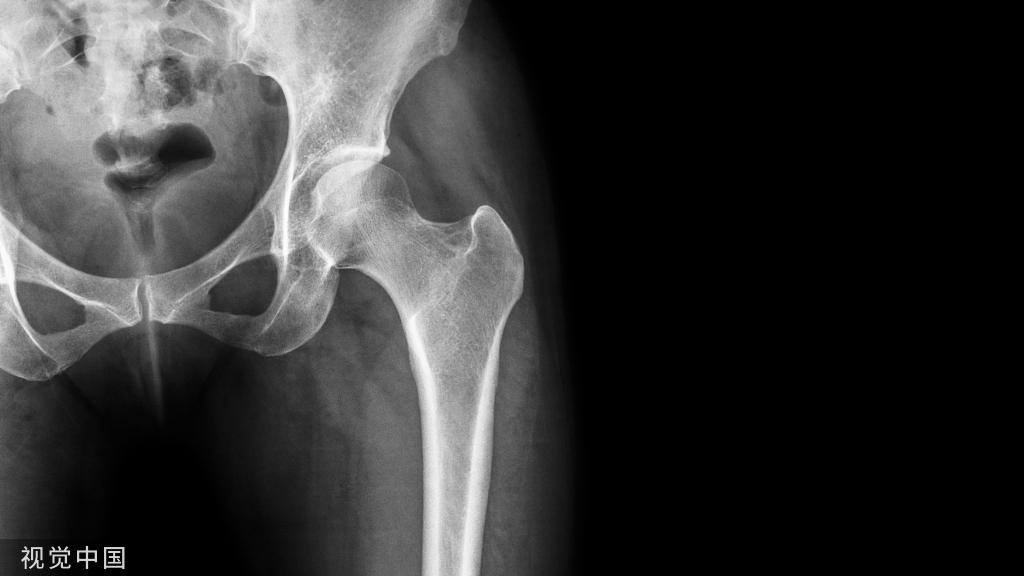

骨折后患者在固定制动期间,如果每周骨量丢失≥0.9%,或总的骨量丢失≥3.6%时,与正常对照组比较差异有统计学意义。因此认为,符合以上两项中的任一标准即可判断为急性骨丢失。骨密度(BMD)是衡量骨量大小的一项重要参考指标。目前,临床上测量BMD的检查方法众多,如X线法、X光密度法、单光子吸收法(SPA)、双光子吸收法(DPA)、双能量X线吸收法(DEXA)、定量CT法(QCT)、定量超声检查法(QUS)等,但比较常用的方法为X线法、DEXA、QCT、QUS和核素骨显像等方法。

X线骨密度检测:X线检测骨密度是一种比较传统的方法,其灵敏度较低,判断误差较大。临床中应用仅仅是将其作为一种初筛BMD的测量方法,通过视觉评估X线片上骨骼皮质厚度、骨小梁粗细程度以及与软组织密度的差异,进而评估有无BMD的改变。仅在严重骨丢失的患者(骨量丢失30%~50%)中可观察到显著的差异。